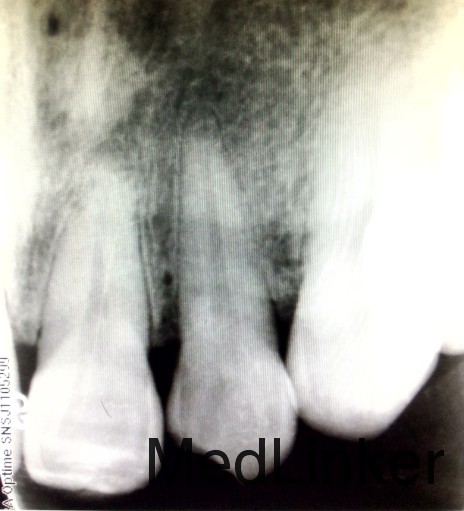

检查:#22近中切角崩缺,未露髓,探-,扣-,松-。邻牙未见明显牙体折断。牙龈稍红,探诊出血。X线示:#22近中切角缺损,未及髓。#21及#22根尖周可见弥散密度减低区。电测示:#21及#22活力存。

诊断:牙折断。 治疗:告知患者该牙目前活力存,但有可能发展为牙髓坏死,建议先行充填治疗,观察患牙,定期检查。 予树脂充填,嘱患者切不可咬硬物。不适随诊,若出现牙髓炎症状、牙髓坏死症状,则行RCT治疗。 定期观察牙槽骨密度减低区。

牙外伤是口腔科常见疾病。牙外伤后患者可能出现“休克”,导致牙髓活力电测试出现假阴性结果,从而误以为牙髓已经坏死。其活力可在6~8周时恢复。因此,牙外伤的患者不可将电测结果作为判断牙髓坏死的依据。对于牙外伤但没有露髓、没有出现牙髓炎症状的患牙,应该观察,必要时及时行根管治疗。此例患者,拍片发现其根尖周有弥散阴影,猜测牙髓可能已经受到影响了,但电测显示其还是有活力的,且没有牙髓炎、根尖周炎症状,故对患者解释之后建议定期观察,必要时再行根管治疗。